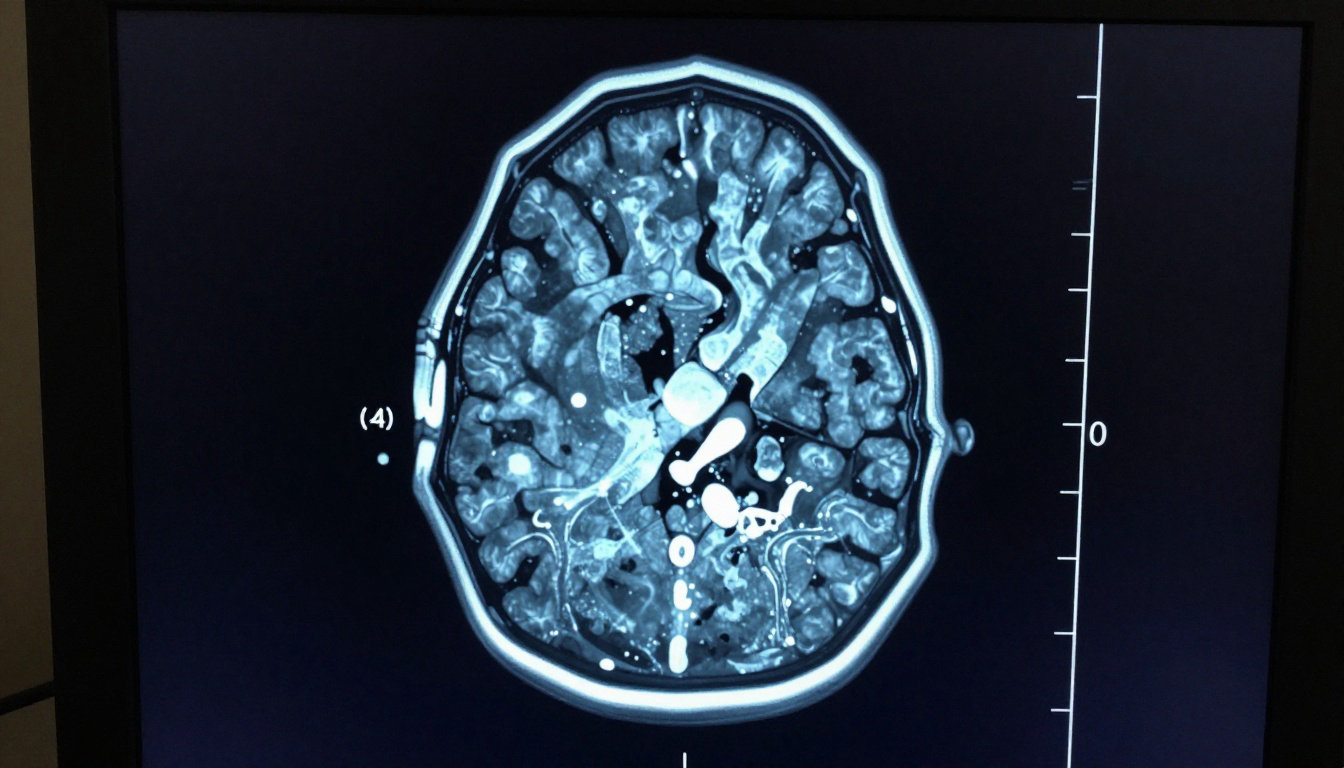

Pathophysiology of the Basal Ganglia Loop

Understanding these physical symptoms requires a look at the complex neural circuits governing our every move.

Dysfunction in the Thalamocortical Circuit

The brain uses a complex loop for signaling. The thalamocortical circuit acts as the primary highway. It connects motor planning with actual muscle execution. Disruptions here lead directly to motor inhibition.

The basal ganglia act as a gatekeeper. They filter out unwanted movements. When they fail, the “go” signal is suppressed.

This failure results in the characteristic slowness. The motor cortex receives insufficient stimulation. Voluntary actions become difficult to produce.

Neurotransmitter Roles of Dopamine and GABA

Dopamine depletion is the core chemical issue. It occurs within the substantia nigra. Without it, the motor circuit loses its balance.

Research indicates that hypokinesia stems from the perte des cellules dopaminergiques et l’hyperactivité de la voie indirecte. This disruption creates a persistent brake on movement. The system fails to initiate motor commands effectively.

GABA plays a massive inhibitory role here. It overpowers the signals needed for movement. This chemical imbalance stops smooth motor flow.

Impact of Glutamate on Motor Control

Glutamate provides excitatory influence on the subthalamic nucleus. Overactivity in this pathway causes further suppression. It creates a “braking” effect on movement.

These chemical shifts are not just abstract. They correlate directly with observable clinical symptoms. Doctors use this knowledge to target specific treatments. Balancing these neurotransmitters is a delicate task.